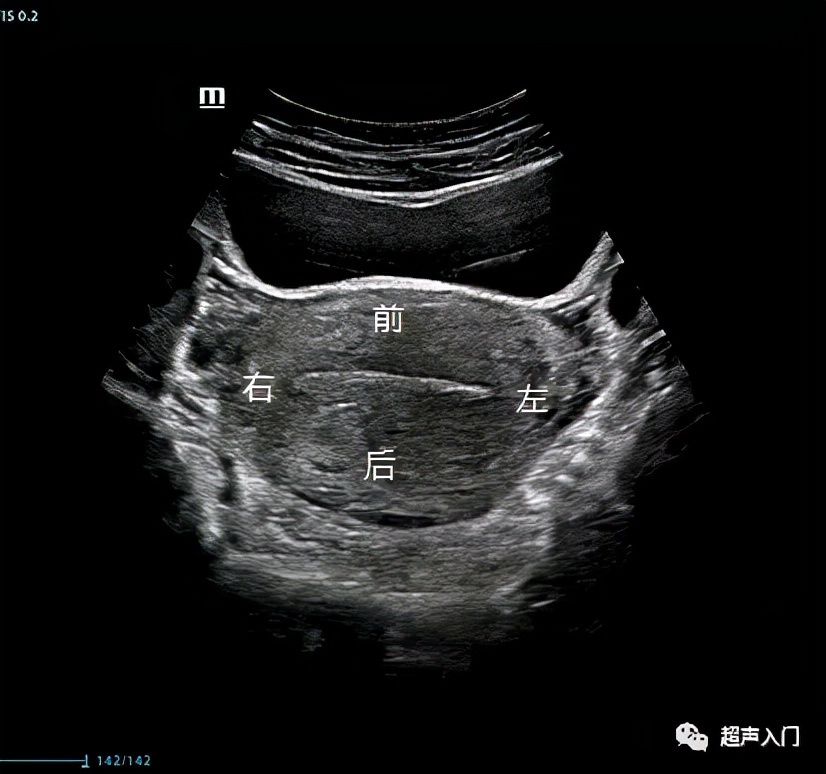

首先我们一起来了解经腹部超声看子宫如何区分前后。当宫体向前(腹壁侧)倾向的时候,我们就说此刻子宫为前位,同理,靠前方的子宫壁,也就称为前壁,子宫壁距离人体背侧近的时候为后壁。

所以经腹部看的超声不管是前平后位子宫,靠近腹侧的子宫壁就称为前壁。